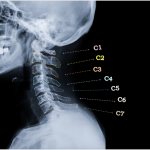

• остеохондроз шейного отдела позвоночника;

Травматическая. Нарушение кровоснабжения глазного дна может быть вызвано механическими повреждениями. Особенно часто ангиопатия развивается после черепно-мозговых травм и в результате нарушения целостности верхних отделов позвоночника.